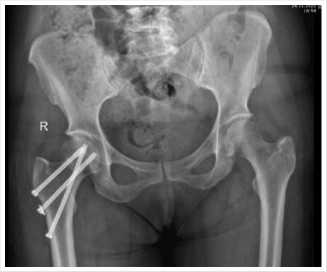

Рис. 2. Контрольная рентгенограмма костей таза после операции.

Раны ушиты наглухо послойно. Асептическая повязка со спиртом. Кровопотеря минимальная. На контрольных снимках положение отломков удовлетворительное, положение отломков правильное (Рис. 2).